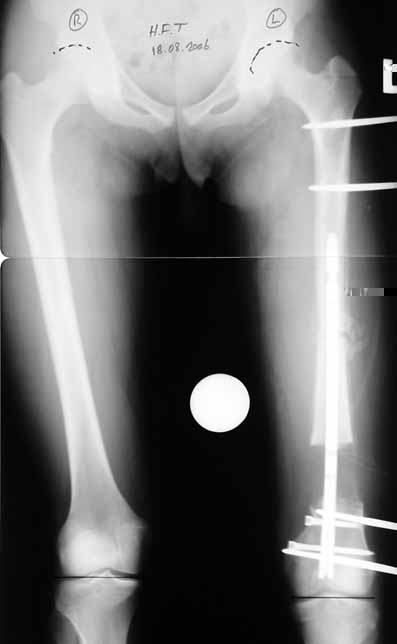

Bu Bacak Kısalık tipi bir kırığın kısalmış pozisyonda kaynaması ile oluşur. Bir çok vaka yetişkinlerde görülür ve sadece bir uzatma ile tedavi edilebilir. Ek deformiteler de aynı anda düzeltilebilir. Bu hastaların çoğu çivi üzerinden uzatma veya tam implante edilen çivi ile tedavi edilebilirler.

Vaka 2